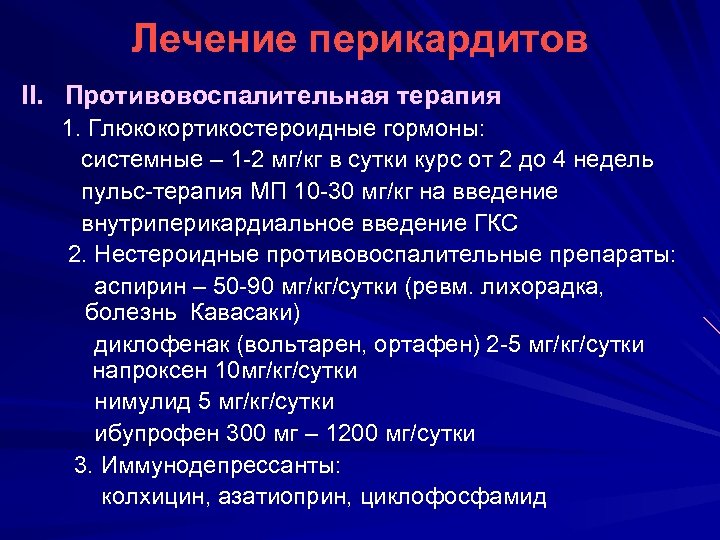

Лечение перикардитов II. Противовоспалительная терапия 1. Глюкокортикостероидные гормоны: системные – 1 -2 мг/кг в сутки курс от 2 до 4 недель пульс-терапия МП 10 -30 мг/кг на введение внутриперикардиальное введение ГКС 2. Нестероидные противовоспалительные препараты: аспирин – 50 -90 мг/кг/сутки (ревм. лихорадка, болезнь Кавасаки) диклофенак (вольтарен, ортафен) 2 -5 мг/кг/сутки напроксен 10 мг/кг/сутки нимулид 5 мг/кг/сутки ибупрофен 300 мг – 1200 мг/сутки 3. Иммунодепрессанты: колхицин, азатиоприн, циклофосфамид